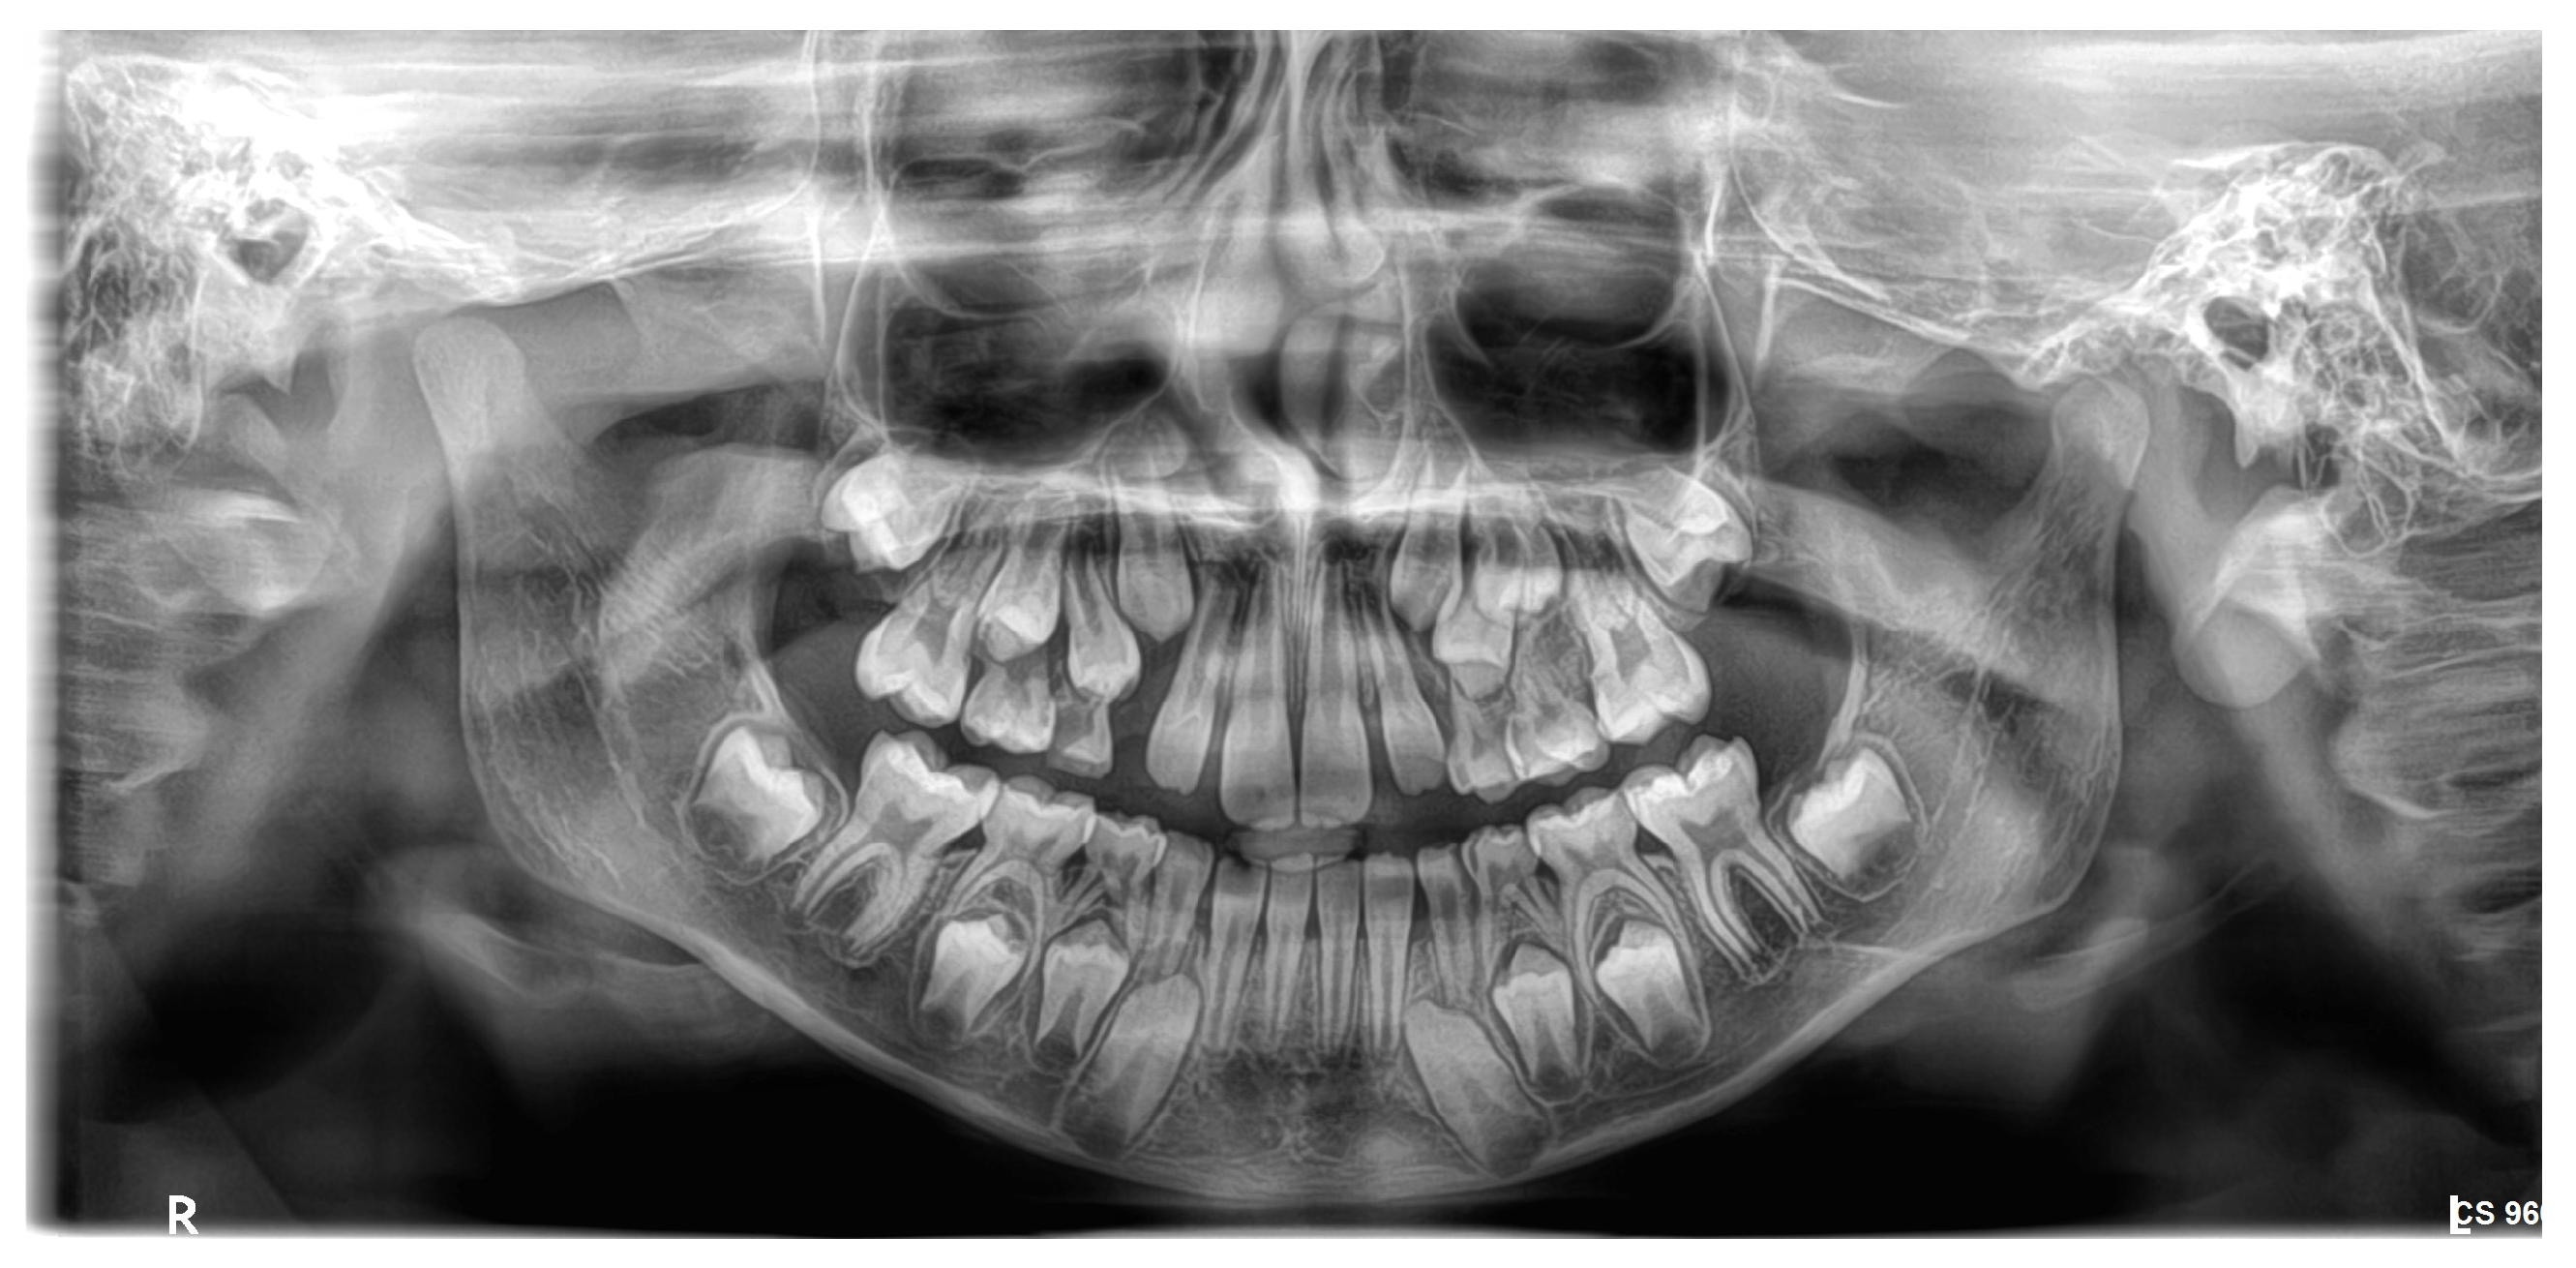

A total of 1200 digital OPGs were collected retrospectively from academic and private dental centers. The sample was 600 males and 600 females aged 8–16. The inclusion criteria were OPGs with adequate quality; both the lower 2nd molars and canines are clearly visualized as in Figure 1, no systemic disease, craniofacial syndrome, and no previous orthodontic treatment. Examinations with inadequate image quality, overlapping dental structures, or incomplete records were excluded.

Figure 1.

Both the lower 2nd molars and canines are clearly visualized as in OPG image.